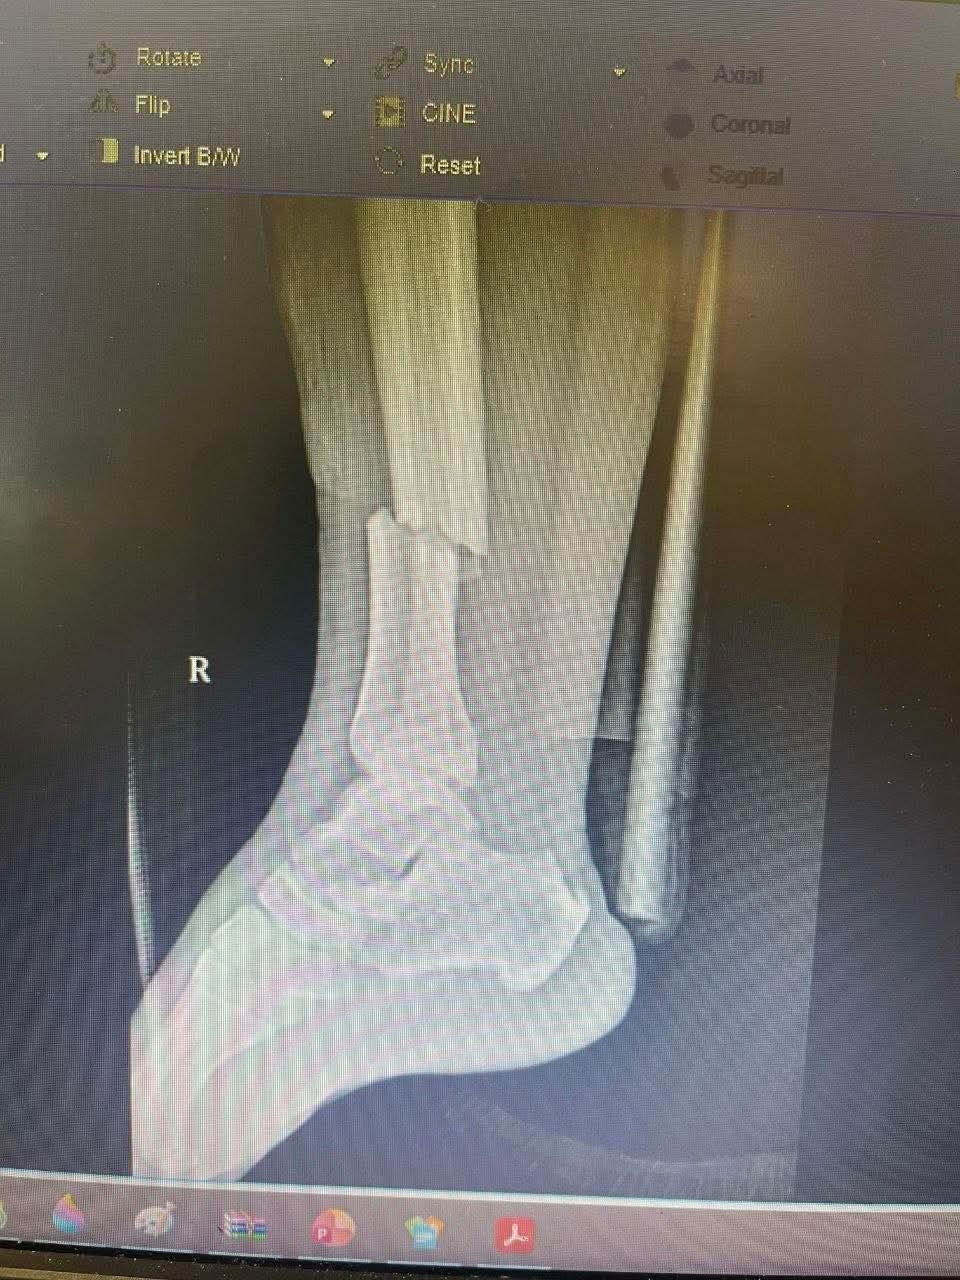

ភ្នំពេញ ៖ ជនសង្ស័យម្នាក់ដែលធ្វើសកម្មភាពឆក់ ត្រូវបានកម្លាំងនគរបាល ខណ្ឌសែនសុខស្រាវជ្រាវនិងដេញឃាត់ខ្លួនបានកាលពីរសៀលថ្ងៃទី២៨ ខែមេសា ឆ្នាំ២០២៦ នៅផ្លូវលេខ២០១១ សង្កាត់គោកឃ្លាង ។ ខណះនោះលោកវរសេនីយ៍ត្រី ដេត ឧត្តម នាយផ្នែកព្រហ្មទណ្ឌ នៃអធិការដ្ឋាននគរបាលខណ្ឌសែនសុខ បានរងរបួសបាក់ជើង ក្នុងករណីដេញបង្ក្រាបមុខសញ្ញាចោរឆក់នេះផងដែរ។

គួរបញ្ជាក់ថា នាយផ្នែកព្រហ្មទណ្ឌនគរបាលខណ្ឌសែនសុខរូបនោះបានរងរបួសបាក់ជើងបន្ទាប់ពីដេញឃាត់ជនសង្ស័យ ហើយជួបគ្រោះថ្នាក់ចរាចរណ៍។បន្ទាប់ពីរងគ្រោះមន្ត្រីនគរបាលព្រហ្មទណ្ឌរូបនោះត្រូវបានថ្នាក់លើយកចិត្តទុកដាក់យ៉ាងខ្លាំងបញ្ជូនទៅ សម្រាកព្យាបាលនៅមន្ទីរមិត្តភាពកម្ពុជាចិនហៅមន្ទីរពេទ្យព្រះកុសមៈ ។ នៅក្នុងនោះឯកឧត្តម ឃួង ស្រេង អភិបាល នៃគណៈអភិបាលរាជធានីភ្នំពេញ និងលោកជំទាវ ជា ស៊ីណា បានជួយនឧបត្ថម្ភថវិកា ៤.០០០.០០០ រៀល ព្រមទាំងមានការជួយឧបត្ថម្ភពីសប្បុរសជន ផងដែរ៕